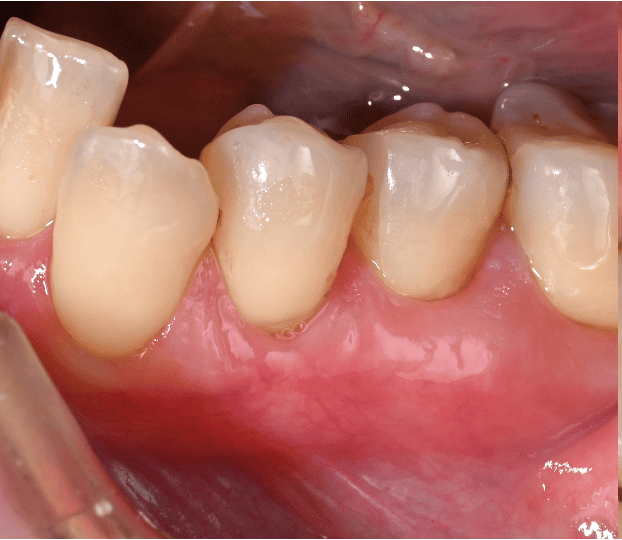

歯肉退縮治療例 治療例1: 40代 女性 ・歯茎が下がってきて、歯が染みてきた 治療前 治療後2年 治療期間 3ヶ月 治療費 5万/1本 (税別) 主な治療内容と概要 根面被覆術(結合組織移植術+歯肉弁歯冠側移動術) 左上の犬歯が伸びてきて染みるということで当院に来院されました。虫歯などはなく、歯茎が下がったことにより根の表面が露出し、知覚過敏の症状がでていました。知覚過敏の改善にはいくつかの方法がありますが、今回は見た目の改善などの患者さんの希望のため、歯肉を移植し、根を覆う処置を行いました。術後から染みの症状はなくなり、歯茎の位置も改善して満足されております。 考えられるリスク・副作用・注意点等 術後の歯肉退縮の再発予防のために決められた指導を守り、継続的なメインテナンスが必要 術後の痛みや腫れなどの症状がでることがあります。(基本的には鎮痛剤の服用などでおさまります) 治療例2: 60代 女性 ・歯ブラシをすると歯茎が痛くて出血する 治療前 犬歯の歯茎だけが大きく下がってしまい、歯の表面が虫歯になりかけている。 治療後1年 歯肉の位置は隣の歯と同様の高さに落ち着き、歯ブラシがしやすい形態に変化した。 治療期間 3ヶ月 治療費 8万/1本 主な治療内容と概要 根面被覆術(歯肉弁側方移動術+結合組織移植術+遊離歯肉移植術) 前歯の一本だけ歯茎が下がってしまい、歯ブラシがしにくい状態になっておりました。そのため、歯茎の炎症と根が一部虫歯に也変えており、今後更に歯茎が下がっていくことが予想されました。組織を移植し、根を覆う処置を行いました。また、硬い歯肉(角化歯肉)が少ないばあい、再発リスクが高くなるため、2回目の手術で硬い歯肉を移植することで、予後が良い状態に改善いたしました。歯肉のラインが横の歯とそろったことで歯ブラシがしやすくなり、現在も良い状態で維持されています。 考えられるリスク・副作用・注意点等 術後の歯肉退縮の再発予防のために決められた指導を守り、継続的なメインテナンスが必要 術後の痛みや腫れなどの症状がでることがあります。(基本的には鎮痛剤の服用などでおさまります) 治療例3: 30代 女性 ・これ以上歯茎が下がるのが不安 治療前 複数の歯の歯茎が下がってしまい、見た目や歯ブラシに影響がでている 治療後5年 歯茎の下がりが改善し、長期的に安定している。 治療期間 3ヶ月 治療費 13万/3本 (止血材込み) 主な治療内容と概要 根面被覆術(トンネリング法+結合組織移植術) 全体的に歯ブラシがお上手でしたが、年齢にしては歯茎が下がってしまい、見た目やブラシング時に不安を感じて来院されました。患者様は今後さらに下がることを恐れており、今回の手術を希望されました。複数歯の歯肉退縮のため、トンネリング法という方法で歯肉の下がりを改善しました。治療後5年たった現在も問題なく不安が解消されたと喜んでおられます。 考えられるリスク・副作用・注意点等 術後の歯肉退縮の再発予防のために決められた指導を守り、継続的なメインテナンスが必要 術後の痛みや腫れなどの症状がでることがあります。(基本的には鎮痛剤の服用などでおさまります) 当院では、歯周病専門医による歯肉退縮(歯茎の下がり)を回復する治療を行っております。 歯茎の位置を元に戻すことで、様々な不具合を改善することができます。また、歯肉を移植する方法を多くとりますが、歯肉を移植することで歯肉の厚みが保たれ、将来的に歯茎が下がることを予防することができます。 矯正治療などにより歯茎が下がった、また歯茎がすでに下がっており、矯正治療できないと言われたなど矯正治療に伴う歯肉退縮改善治療も多く行っています。ご紹介していただく場合は、担当の先生と矯正の開始時期等についてもご相談し、最適な時期に行うことができます。 もしご質問や治療ご希望の患者様はご予約の際に受付にお申し付けください。 歯科鈴木医院 (板橋区桜川 東武鉄道東上本線上板橋から徒歩7分) 2020.12.18 実際の治療例 治療例 本ページでは、当院での実際の治療例を示しております。 各治療例で紹介している治療による結果は個人差があり、治療効果を保証するものではありません。また、起こりうるリスクや副作用等を十分に理解し、担当医と相談して選択し… 2023.05.11 歯周病治療 治療例 歯周病治療例 治療例1: 40代 男性 ・歯医者が怖くてずっと行けていなかった。 ・歯が揺れてきて噛めない ・血が出るので歯ブラシが怖くてできない 治療前 … 2018.06.10 歯周病治療 トップページ 〉診療案内〉歯周病治療 歯周病認定医・専門医とは 歯周組織再生療法 歯周病とは? あなたは以下の項目のどれか当てはまることがありますか? ・朝起きたとき、口の中がネバネバする。 ・ブラッシング時に出…